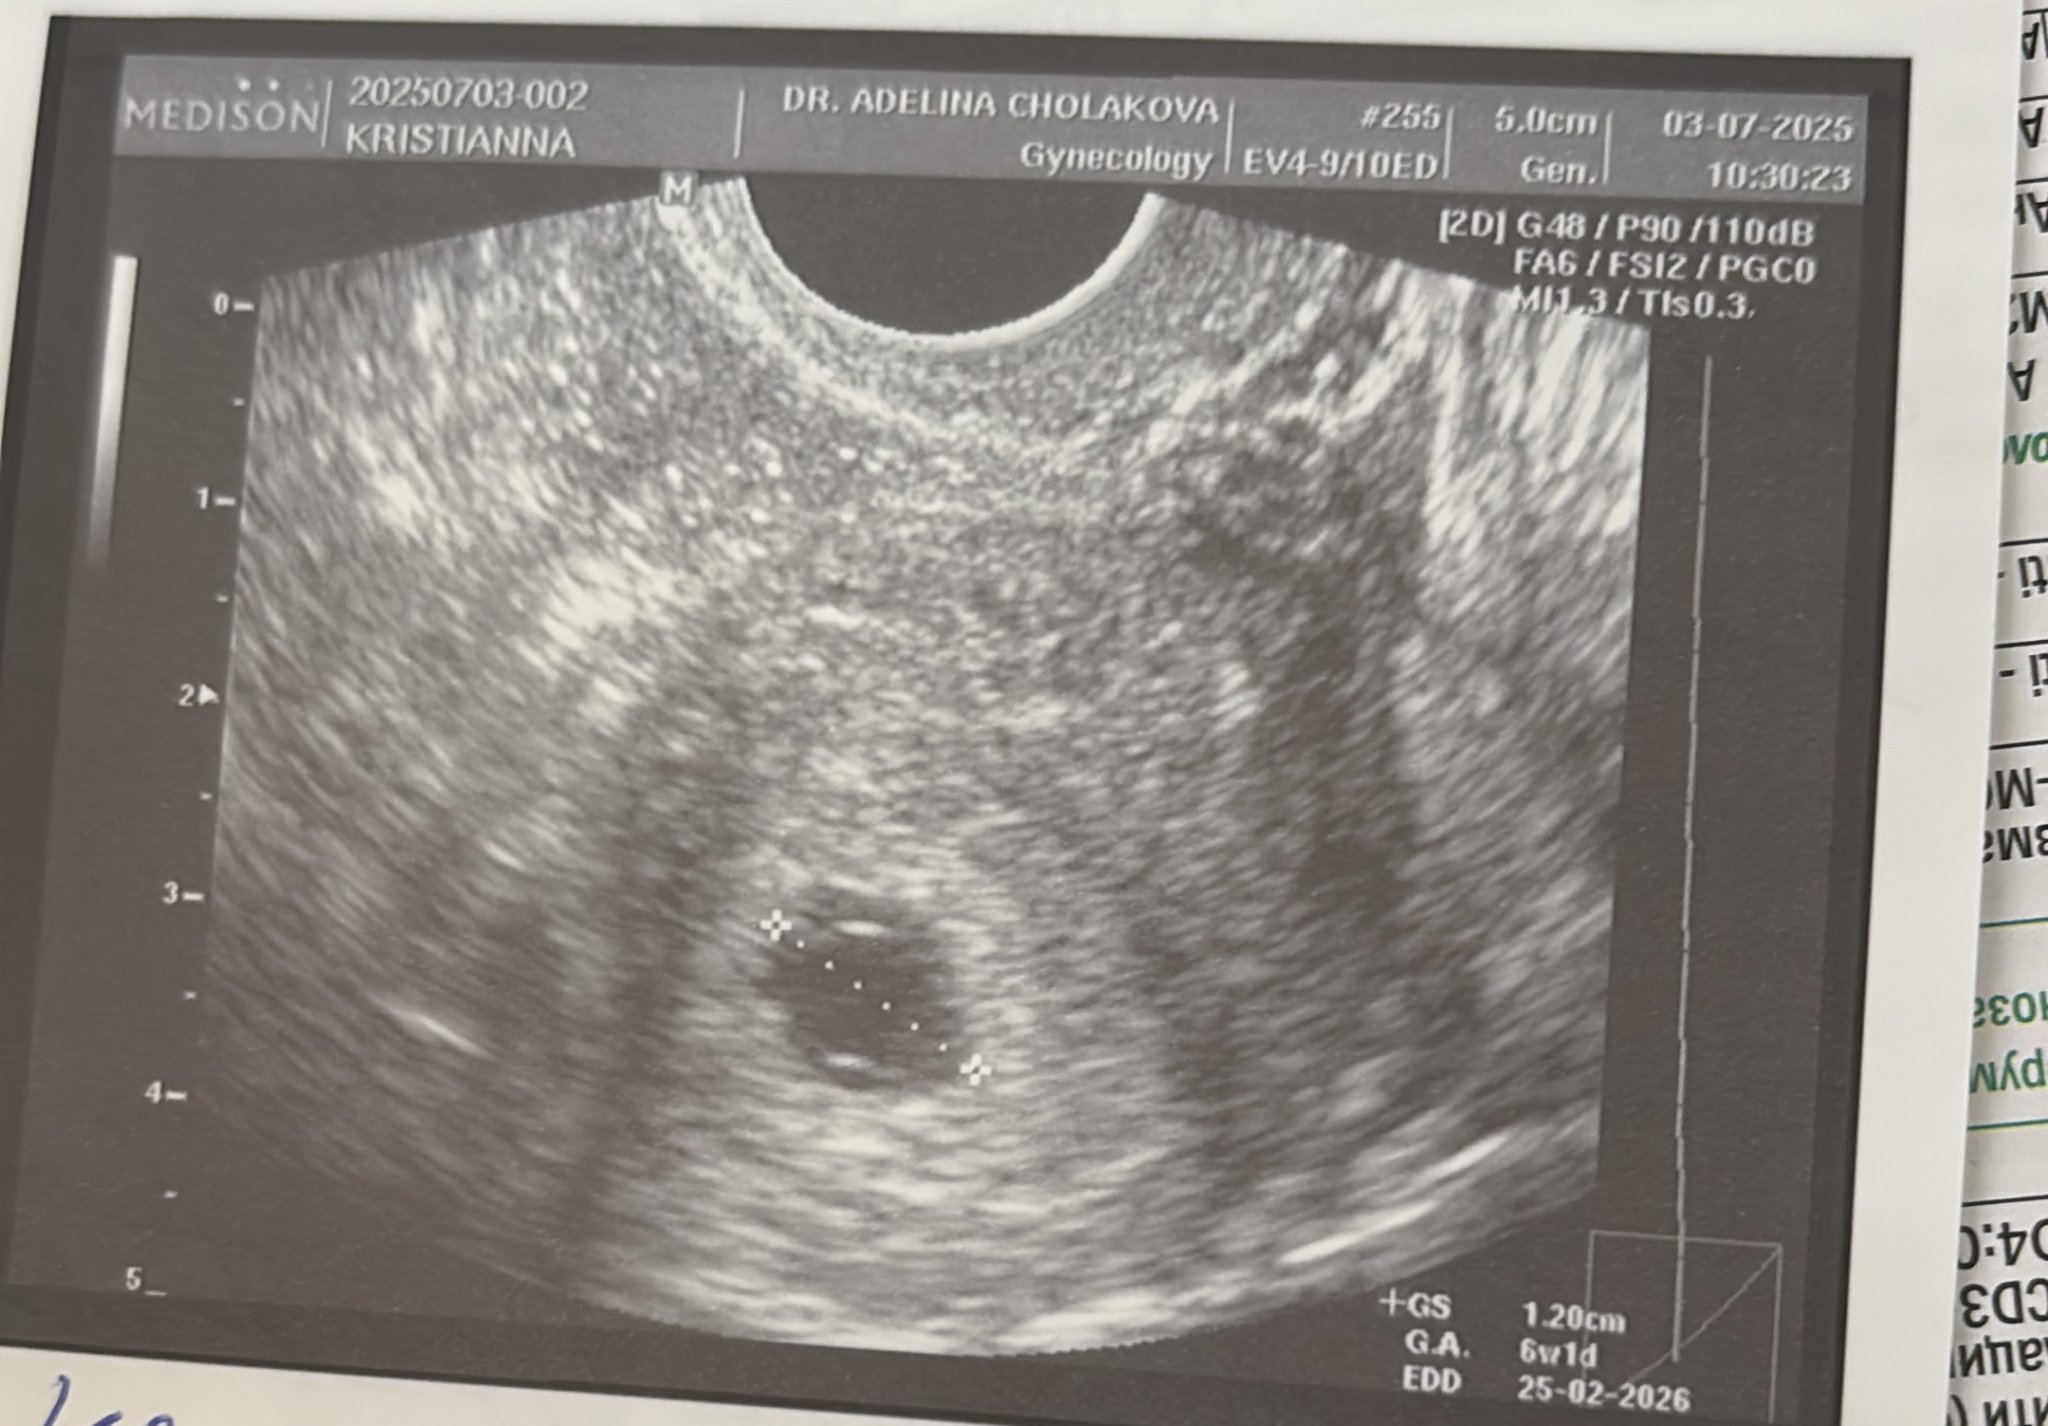

Какво представлява изображението от ехографията на 5-седмична и 2-дневна бременност?